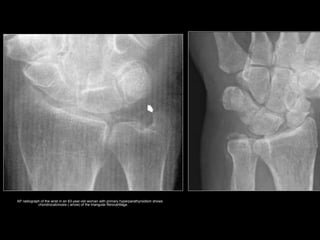

AP radiograph of the wrist in an 83-year-old woman with primary hyperparathyroidism shows

chondrocalcinosis ( arrow) of the triangular fibrocartilage.

Radiologic findings ofRadiologic findings of

HYPERPARATHYROIDISMHYPERPARATHYROIDISM

PrimaryPrimary

• Chondrocalcinosis

• usually seen in the

menisci of the

knee, the

triangular

fibrocartilage of

the wrist, and the

pubic symphysis